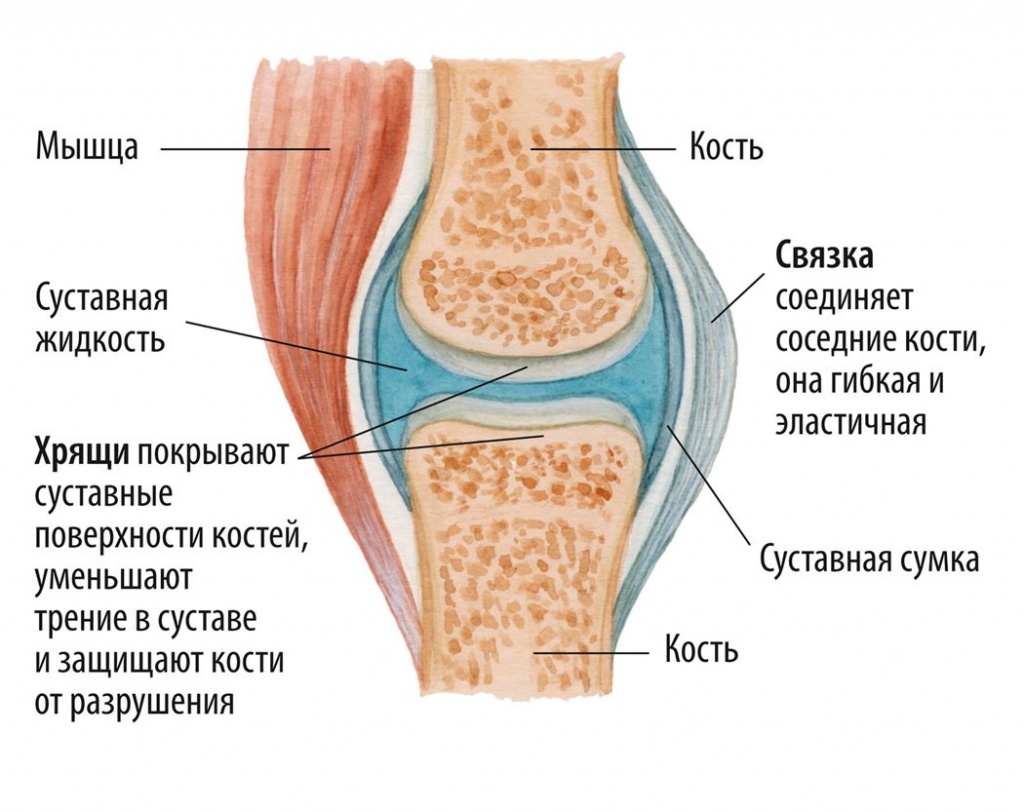

Рисунки Суставов: Анатомические Иллюстрации